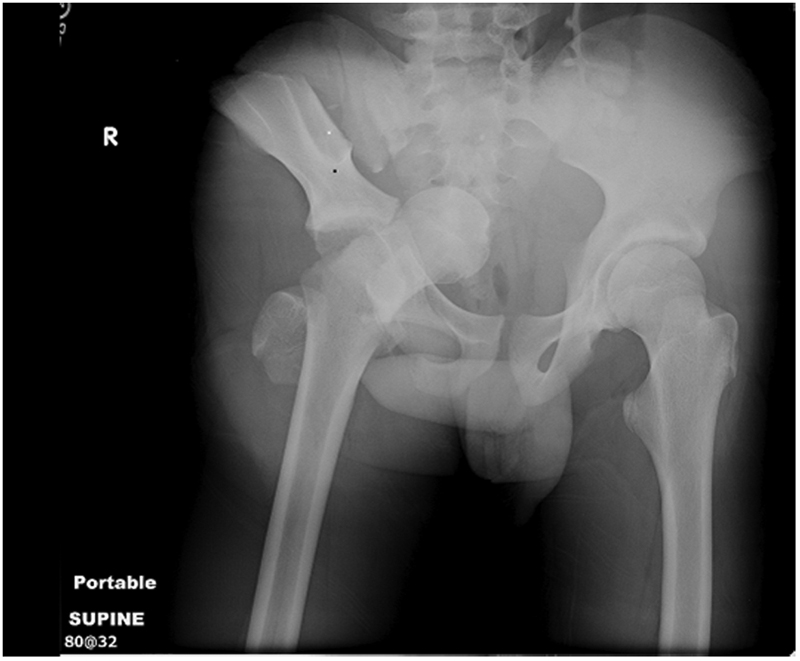

DESIGN: Patients were separated into body mass index (BMI) quartiles, with BMI calculated as weight in kilograms divided by height in meters squared. From each BMI quartile, 30 patients were randomly chosen for inclusion in the study on the basis of a priori power analysis (n = 120). Chest wall thickness on computed tomography at the second ICS in the MCL was compared with the fifth ICS in the AAL on both the right and left sides through all BMI quartiles.

RESULTS: A total of 680 patients met the study inclusion criteria (81.5% were male and mean age was 41 years [range, 16-97 years]). Of the injuries sustained, 13.2% were penetrating, mean (SD) Injury Severity Score was 15.5 (10.3), and mean BMI was 27.9 (5.9) (range, 15.4-60.7). The mean difference in chest wall thickness between the second ICS at the MCL and the fifth ICS at the AAL was 12.9 mm (95% CI, 11.0-14.8; P < .001) on the right and 13.4 mm (95% CI, 11.4-15.3; P < .001) on the left. There was a stepwise increase in chest wall thickness across all BMI quartiles at each location of measurement. There was a significant difference in chest wall thickness between the second ICS at the MCL and the fifth ICS at the AAL in all quartiles on both the right and the left. The percentage of patients with chest wall thickness greater than the standard 5-cm decompression needle was 42.5% at the second ICS in the MCL and only 16.7% at the fifth ICS in the AAL.